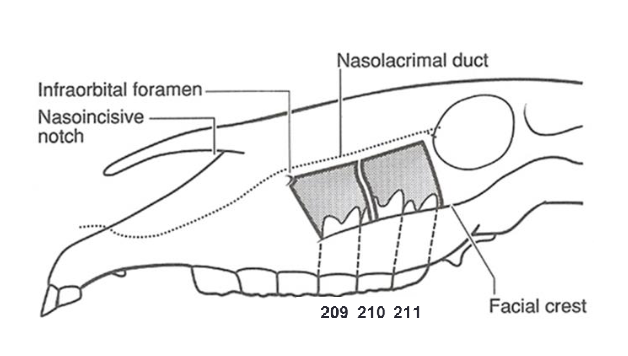

dental anatomy- triadan system

1-upper right

2-upper left

3- lower left

4-lower right

x01= first incisor

x04= canine

x05= wolf tooth

x08= last premolar

x09= first molar

paranasal sinuses

frontal

maxillary (rostral and caudal compartments)

sphenopalatine

dorsal conchal

middle conchal

ventral conchal

bold= clinically relevant

frontal sinus: ethmoid hematoma

mild, intermittent, unilateral, spontanous epistaxis (bloody nose)

smooth, glistening mottled green surface

unknown cause

maxillary sinuses

109/209 teeth communicate w/ rostral compartment

110/210 and 111/211 communicate w/ caudal compartment

tooth root infections =

secondary sinusitis